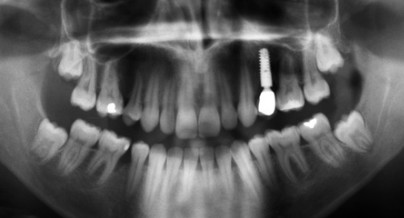

In der Zahnmedizin gehört die radiologische Untersuchung zu den Standardmaßnahmen. Zu diesem Zweck hat sich die Panoramaschichtaufnahme als Grundlage jeder systematischen Röntgenuntersuchung etabliert15 (Abb.2).

Abb. 2: Panoramaschichtaufnahme eines Patienten aus der Eingangsuntersuchung.

Die Panoramaschichtaufnahme ermöglicht eine umfassende Beurteilung der Zähne und der benachbarten Strukturen, speziell der knöchernen, und kann somit eine Vielzahl von Zusatzbefunden (aber auch Zufallsbefunden) liefern. Dadurch ist es möglich, bei relativ geringer Strahlenbelastung Knochenabbau und Karies sowie Anomalien zu erfassen. Dies sollte laut Pasler (2003) die „routinemäßige“ Anfertigung einer Panoramaschichtaufnahme rechtfertigen, sie sollte demgemäß auch bei der Erstuntersuchung neuer Patienten aller Altersgruppen durch- geführt werden. Mit einer ergänzenden radiologischen Untersuchung kann somit ei-ne komplette Befunderhebung möglich sein.15

Als Nachteile sind jedoch die technikbedingten Unschärfen und Ungenauigkeiten durch den nicht konstanten Fokus-Objekt-Abstand aufzuführen. So resultiert immer eine Vergrößerung (Oberkiefer um 27%, Unterkiefer um 26%) der abgebildeten Strukturen.2 Daraus ergibt sich, dass genaue Messungen an einer Panoramaschichtaufnahme nicht möglich sind. Weiterhin überlagern sich die Strukturen und pathologische Veränderungen können dadurch vorgetäuscht werden.15 Besonders die Frontzahnregion im Oberkiefer ist davon betroffen; eine exakte Befundung dieser Region anhand einer Panoramaschichtaufnahme ist somit schwierig.15 Darüber hinaus ist sie zur Diagnostik initialer parodontaler Läsionen wenig geeignet, da beginnender Knochenabbau häufig unterschätzt wird.2,8,12 Zudem kann der Verlauf des Limbus alveolaris lediglich im approximalen Bereich eindeutig beurteilt werden. Bei manifestem Knochenabbau ist die Pano- ramaschichtaufnahme hingegen zuverlässig und somit für die Diagnostik, Charakterisierung und Überwachung einer fortgeschrittenen Parodontitis unverzichtbar.8,9,12,18 Grundsätzlich muss bei der radiologischen Befundung beachtet werden, dass ein Röntgen- bild nicht in der Lage ist, entzündliche Veränderungen der Gingiva zu erfassen.15